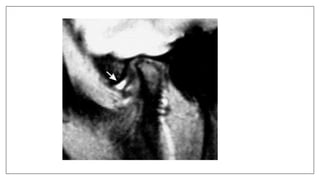

Stuck disk Phenomenon inTMJ

• A stuck disc refers to aTMJ disc which does not translate anteriorly out of

the mandibular fossa onto the articular eminence, but rather remains (thus

"stuck") in the fossa. It is a form ofTMJ dysfunction and is typically

associated with restricted range of motion.

• Its due to fibrous adhesions

Campos PS, Macedo Sobrinho JB, Crusoé-Rebello IM, Pena N, Dantas JA, Mariz AC, et al.Temporomandibular joint disk

adhesion without mouth-opening limitation. J Oral Maxillofac Surg. 2008;66(3):551-4. doi:10.1016/j.joms.2006.11.006